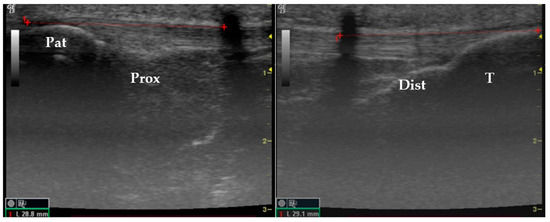

2.3. Data Collection